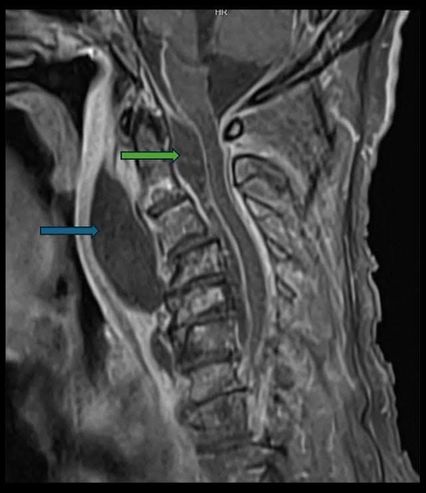

“ที่ห้องฉุกเฉิน แพทย์เห็นว่า ลิ้นไก่ของผู้ป่วยถูกดันไปด้านหน้า คอด้านหลังบวมเหมือนมีอะไรมาดัน และผู้ป่วยเริ่มมีเสียงหายใจคล้ายเสียงกรน (stridor) แต่ไม่ได้หลับ เคสนี้ทำ CT และ MRI มีฝีหนองก้อนใหญ่ อยู่ในช่องหลังคอ (retropharyngeal space) กดผนังคอเข้าด้านหน้า จนช่องลมที่ควรโล่ง เหลือแค่นิดเดียว อีกไม่กี่ชั่วโมง อาจปิดทางเดินหายใจได้เลย

จุดเริ่มต้นทั้งหมดมาจาก ฟันผุที่ลุกลาม ทำให้ติดเชื้อไปที่กระดูกขากรรไกร ต่อมน้ำเหลือง โดยช่องหลังคอ เป็นเส้นทางการลุกลามที่อันตรายแบบไม่รู้ตัว มารู้ตัวตอนเริ่มไปคอแล้ว และยังพบว่ามีการลุกลามเข้าไปโพรงเยื่อหุ้มไขสันหลังแล้วด้วย (Epidural abscess)